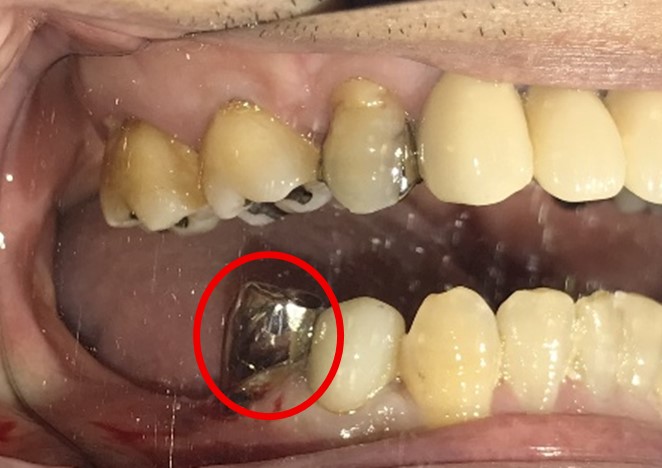

右下奥の歯が、グラグラして噛むと痛い。

治療内容

歯根の周りの骨が全く無い状態でしたので、保存することができず抜歯しました。3本歯がないところに2本インプラントを埋入しました。

Before

※赤丸を抜歯しました。

After